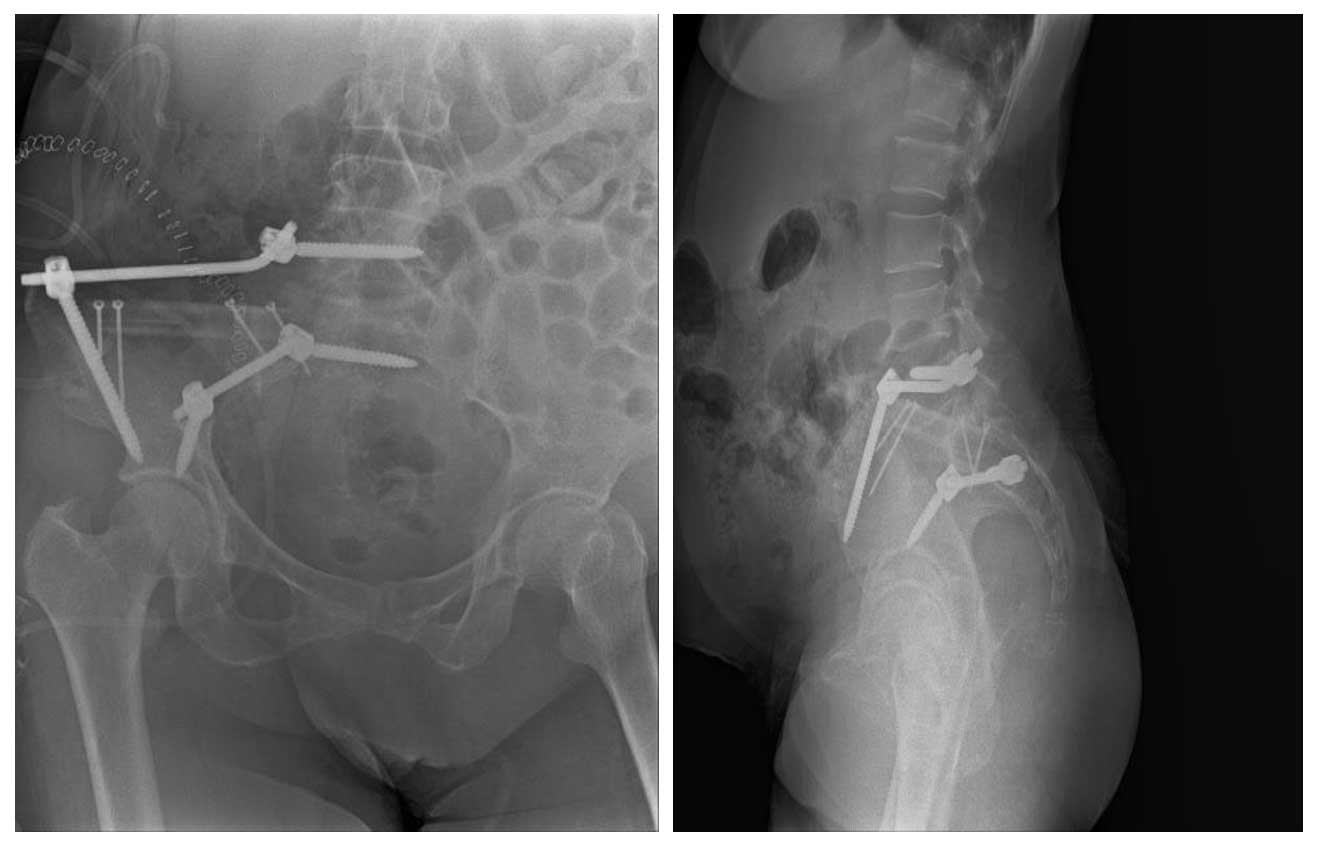

Hastaya geniş rezeksiyon (Tip I hemipelvektomi) uygulanmış, ardından fibula grefti ve rod/vida ile rekonstrüksiyon yapılmıştır.

Ameliyat Sonrası: Röntgende Tip-I hemipelvektomi sonrası fibula ve rod/vida ile rekonstrüksiyon işlemi görülmekte.